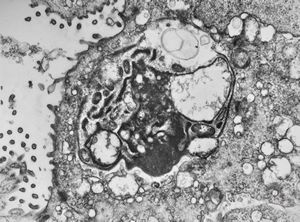

M,46y. | Entamoeba histolytica